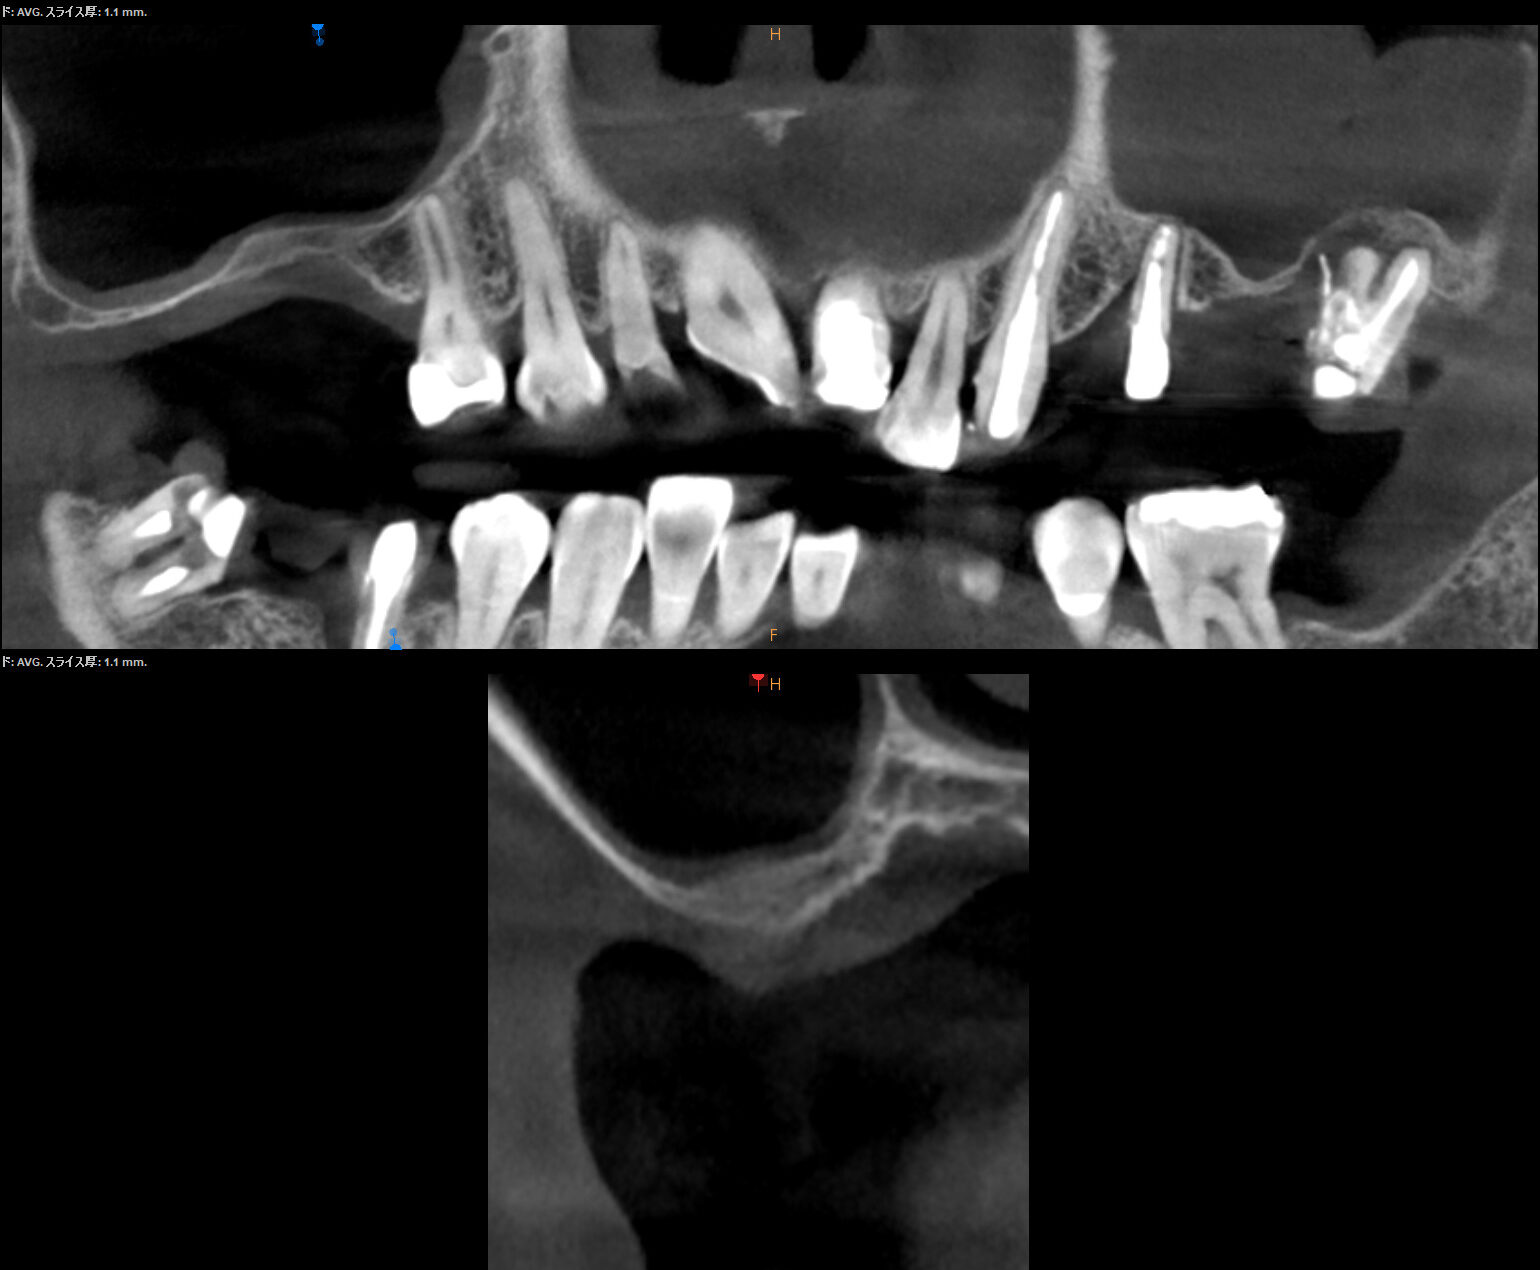

治療前

抜歯を行うと、さまざまな要因で元々あった骨は吸収してしまいます。インプラント治療が困難であるという説明を受ける際の原因の多くはこのためです。

この失われた部分に、人工骨や再生膜を用いて骨の再生を促す治療です。

インプラント治療の際、インプラントを支えるための骨が不足している場合に行われます。

技術的難易度が高く、再生できる骨量も術者依存になることが多いため、執刀医の経験と実績が非常に重要な要素となります。